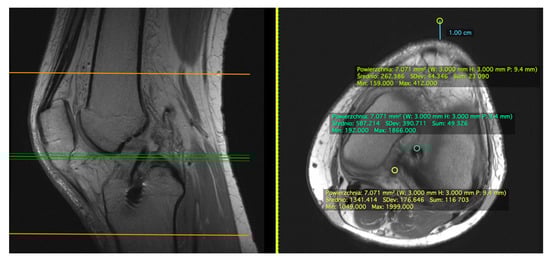

2.1. Measurement on the Sagittal Plane

2.2. Measurement on the Axial Plane